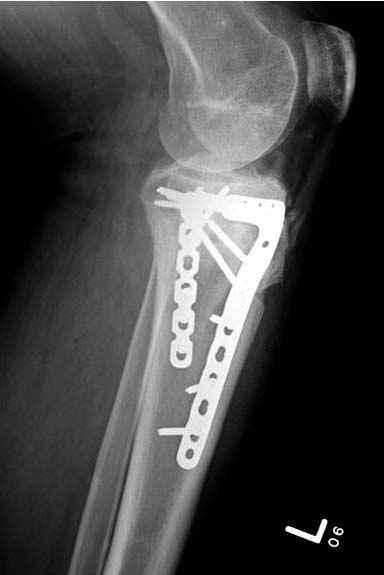

Решили выполнить остеосинтез штифтом и внутрисуставного перелома пластиной и винтами. Жду мнения! Зачем мне оправдываться-я же не преступник. Диалогом называется...

Отдельные переломы тибиал плато и перелом проксимальной трети большеберцовой кости отличаются от переломов тибиал плато с вовлечением диафиза. Здесь перелом тибиал плато типа Schatzker VI, полученный в результате высокоэнергетической травмы. Перелом метафиза образовал отрыв суставной поверхности от диафиза с вовлечением медиального и латерального мыщелков. Двухмыщелковые переломы из-за укрочения опасны развитием компартаментального синдрома, повреждением латерального мениска и связок.

На вашем место я бы подождал с фиксацией до готовности кожных покровов, и за это время можно было подобрать соответствующий фиксатор, т.е более длинная пластина снаружи и медиальная пластина на апексе перелома как подпорка. Здесь приемлем как раз минимальный доступ.

Здесь пару случаев для сравнения,...в первых 1-4 слайдах метод фиксации одним фиксатором, как видно после 8 месяцев сохранилась ось. С 5 по 9 вариант двумя пластинами...